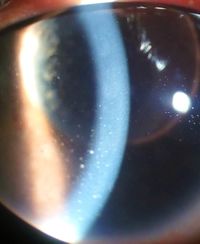

التهاب العين والرواسب القرنية بسبب التهاب القزحية | |

- تشمل علامات التهاب العنبية الأمامي اتساع الأوعية الهدبية، ووجود الخلايا والتوهج في الغرفة الأمامية، والرواسب القرنية ("KP") على السطح الخلفي للقرنية . في حالة الالتهاب الشديد قد يكون هناك دليل على وجود غمير قيحي . يتم التعرف على الحلقات القديمة من التهاب القزحية عن طريق ترسبات الصباغ على العدسة ، و الرواسب القرنية، والحدقة المتطرفة عند اتساع حدقة العين.